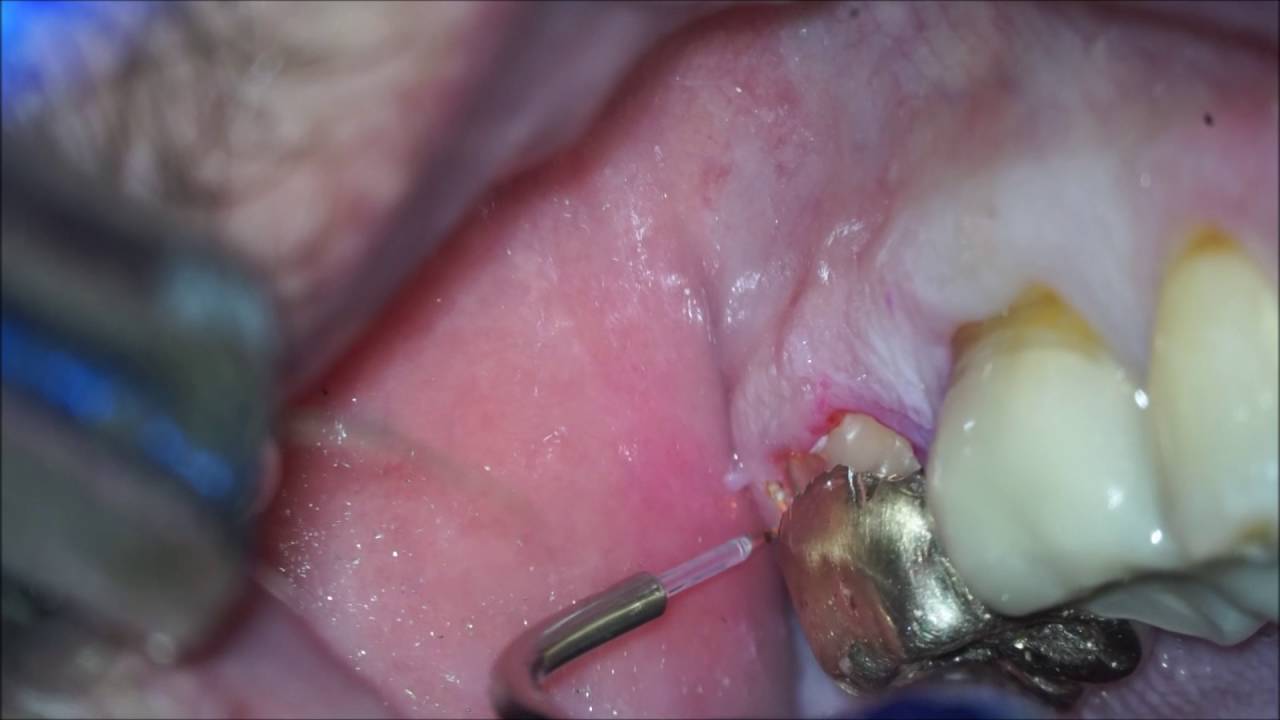

From www.youtube.com

Class II amalgam cavity preparation and restoration YouTube Dental Amalgam Tongue this type of tattoo is actually a side effect of common dental fillings. learn about dental amalgam safety, other materials for dental fillings, and reporting problems with amalgam fillings. This easily moldable substance is then placed and formed into the space where tooth decay has been drilled out, then hardens. Dental amalgam is a safe, affordable and durable. Dental Amalgam Tongue.

18 buccal amalgam patch with narration YouTube Dental Amalgam Tongue mercury poisoning symptoms can arise from dental amalgam fillings, also called silver fillings, as they continuously release mercury vapor. components of amalgam may, in rare instances, cause local side effects or allergic reactions referred to as oral. cnn — the us food and drug administration warned thursday that silver dental fillings, known as dental amalgam, may cause.. Dental Amalgam Tongue.